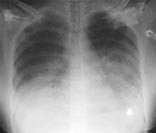

Pasient 2. 29 år gammel tidligere frisk kvinne innlagt med tre dagers sykehistorie. Hun hadde influensasymptomer med muskelverk, ryggsmerter, hodepine og temperatur opp i 40,8 ˚C. Hun var tilsett på poliklinikken dagen i forveien, hun klaget da over tørrhoste. Røntgen thorax var negativt (fig 1) CRP var 178 mg/l, trombocytter 78 _ 109/l og leukocytter 2,5 _ 109/l. Ved innleggelse hadde hun respirasjonsfrekvens på 30, puls 130, temperatur 39,1 ˚C, og røntgen thorax viste nå bilaterale konfluerende fortetninger (fig 2). CRP var steget til 248 ml/l, trombocytter var falt til 60 _ 109/l, det var lett forhøyede transaminaser, normalt kreatininnivå og fibrin degradasjonsprodukter (FDP-DD) var 8,0. Tilstanden ble nå oppfattet som en pneumoni eller sepsis med sjokklungeutvikling. Hun ble satt på behandling med høydose penicillin-G, netilmycin og erytromycin.